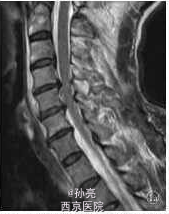

【一般资料】 患者,男,61岁。 【主诉】 因高处坠落致颈部疼痛2h余入院。 【查体】 C4-C6棘突压痛明显,活动受限,稍有肿胀,双上肢感觉麻木伴有痛觉过敏,双侧肱二头肌肌力Ⅳ级,双手握力下降,双下肢感觉活动可,肢端感觉血供可。入院时实验室检查均未见明显异常。MRI检查显示C3-C7椎间盘后突伴C4-C6平面椎管狭窄,颈髓受压,髓内见小片高信号影,颈椎退行性改变(图1a)。 【诊断】 ①颈椎病;②颈髓损伤。 【诊断治疗】 手术植入大小适中填满松质骨的钛网,再将长短合适的颈前路钢板系统通过螺丝钉固定于开槽减压区上下方椎体上。C形臂X线机透视证实钢板系统位置正确后,切口内置负压引流管,逐层缝合切口。手术顺利,出血约200ml。术后48h切口引流量约50ml,拔除引流管。术后复查X线片示内固定位置可(图1b,1c)。术后查体:双上肢感觉无麻木,双侧肱二头肌肌力Ⅳ级强,双手握力Ⅳ级,双下肢各肌群肌力Ⅴ级,感觉活动可。 术后第5天突发神志不清,躁动不安,查体:双上肢肌力Ⅲ级,双下肢肌力0级,病理反射未引出。急查头颅CT、血电解质、血气分析等均未发现明显异常,胸部CT示双肺下叶炎症伴两侧胸膜反应。经相关临床科室会诊后转入ICU监护,予抗感染,加强龙冲击等对症支持治疗。复查头颅MRI、DWI、MRA,胸腰椎MRI均未见明显异常,颈椎MRI示:C4-C6椎体内固定术后改变,颈髓受压,髓内见小片高信号影(图1d)。经外院脊柱外科专家会诊:颈髓受压影像考虑为内固定产生伪影所致。